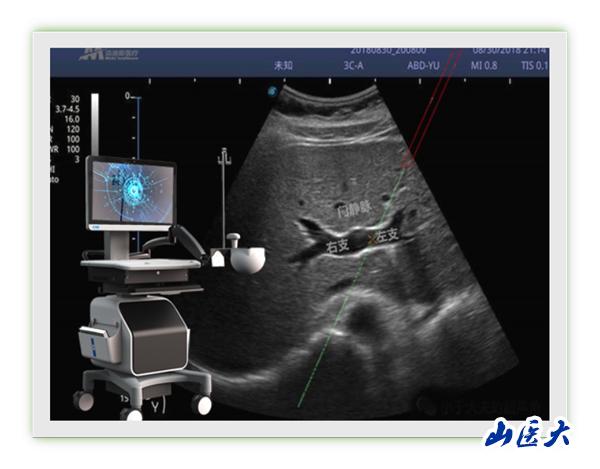

近日,第一医院肿瘤与血管介入科冯对平主任团队成功完成山西省首例超声用电磁定位穿刺引导TIPS术。该技术将超声图像与电磁信号相融合,突破传统超声引导必须在平面内或平面外穿刺制约,能够在任意位置、任意角度、任意平面穿刺靶点,真正实现实时三维穿刺导航。更为重要的是,该技术具有我国自主知识产权。冯对平说:“该新型穿刺引导技术能够大大降低TIPS术中门静脉穿刺难度,提高TIPS手术成功率,同时术者及患者受X线辐射时间也明显缩短,值得进一步推广应用。”